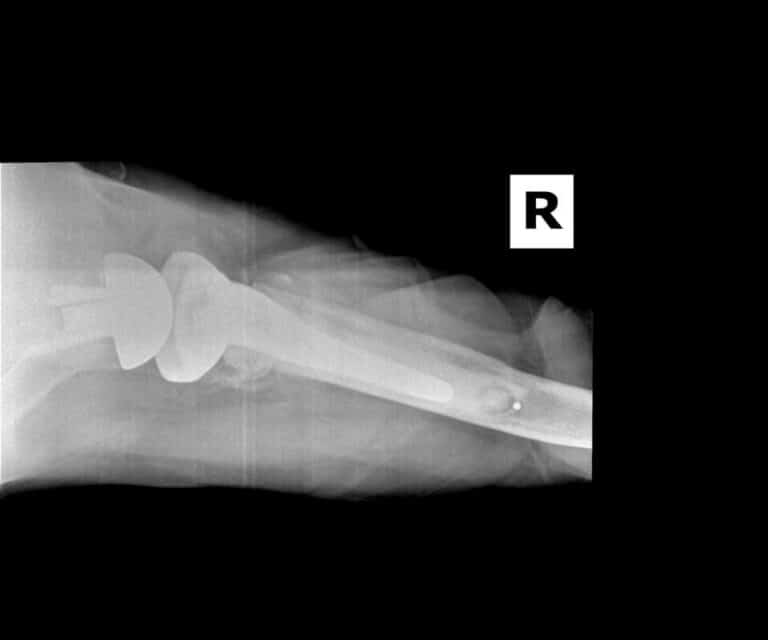

Stryker/Wright/Tornier, Aequalis Fracture